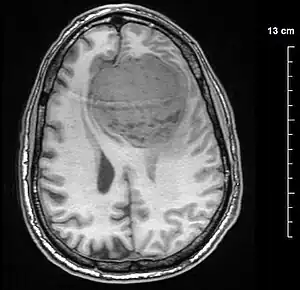

Low-grade and high-grade meningioma. H&E stain.[19]

Meningiomata are visualized readily with contrast CT, MRI with gadolinium,[20] and arteriography, all attributed to the fact that meningiomata are extra-axial and vascularized. CSF protein levels are usually found to be elevated when lumbar puncture is used to obtain spinal fluid. On T1-weighted contrast-enhanced MRI, they may show a typical dural tail sign absent in some rare forms of meningiomas.[16]

Although the majority of meningiomata are benign, they may have malignant presentations. Classification of meningiomata are based upon the WHO classification system.[21]

• Benign (Grade I) – (90%) – meningothelial, fibrous, transitional, psammomatous, angioblastic

• Atypical (Grade II) – (7%) – chordoid, clear cell, atypical (includes brain invasion)

• Anaplastic/malignant (Grade III) – (2%) – papillary, rhabdoid, anaplastic (most aggressive)

In a 2008 review of the latter two categories, atypical and anaplastic-meningioma cases, the mean overall survival for atypical meningiomata was found to be 11.9 years vs. 3.3 years for anaplastic meningiomata. Mean relapse-free survival for atypical meningiomata was 11.5 years vs. 2.7 years for anaplastic meningiomata.[22]